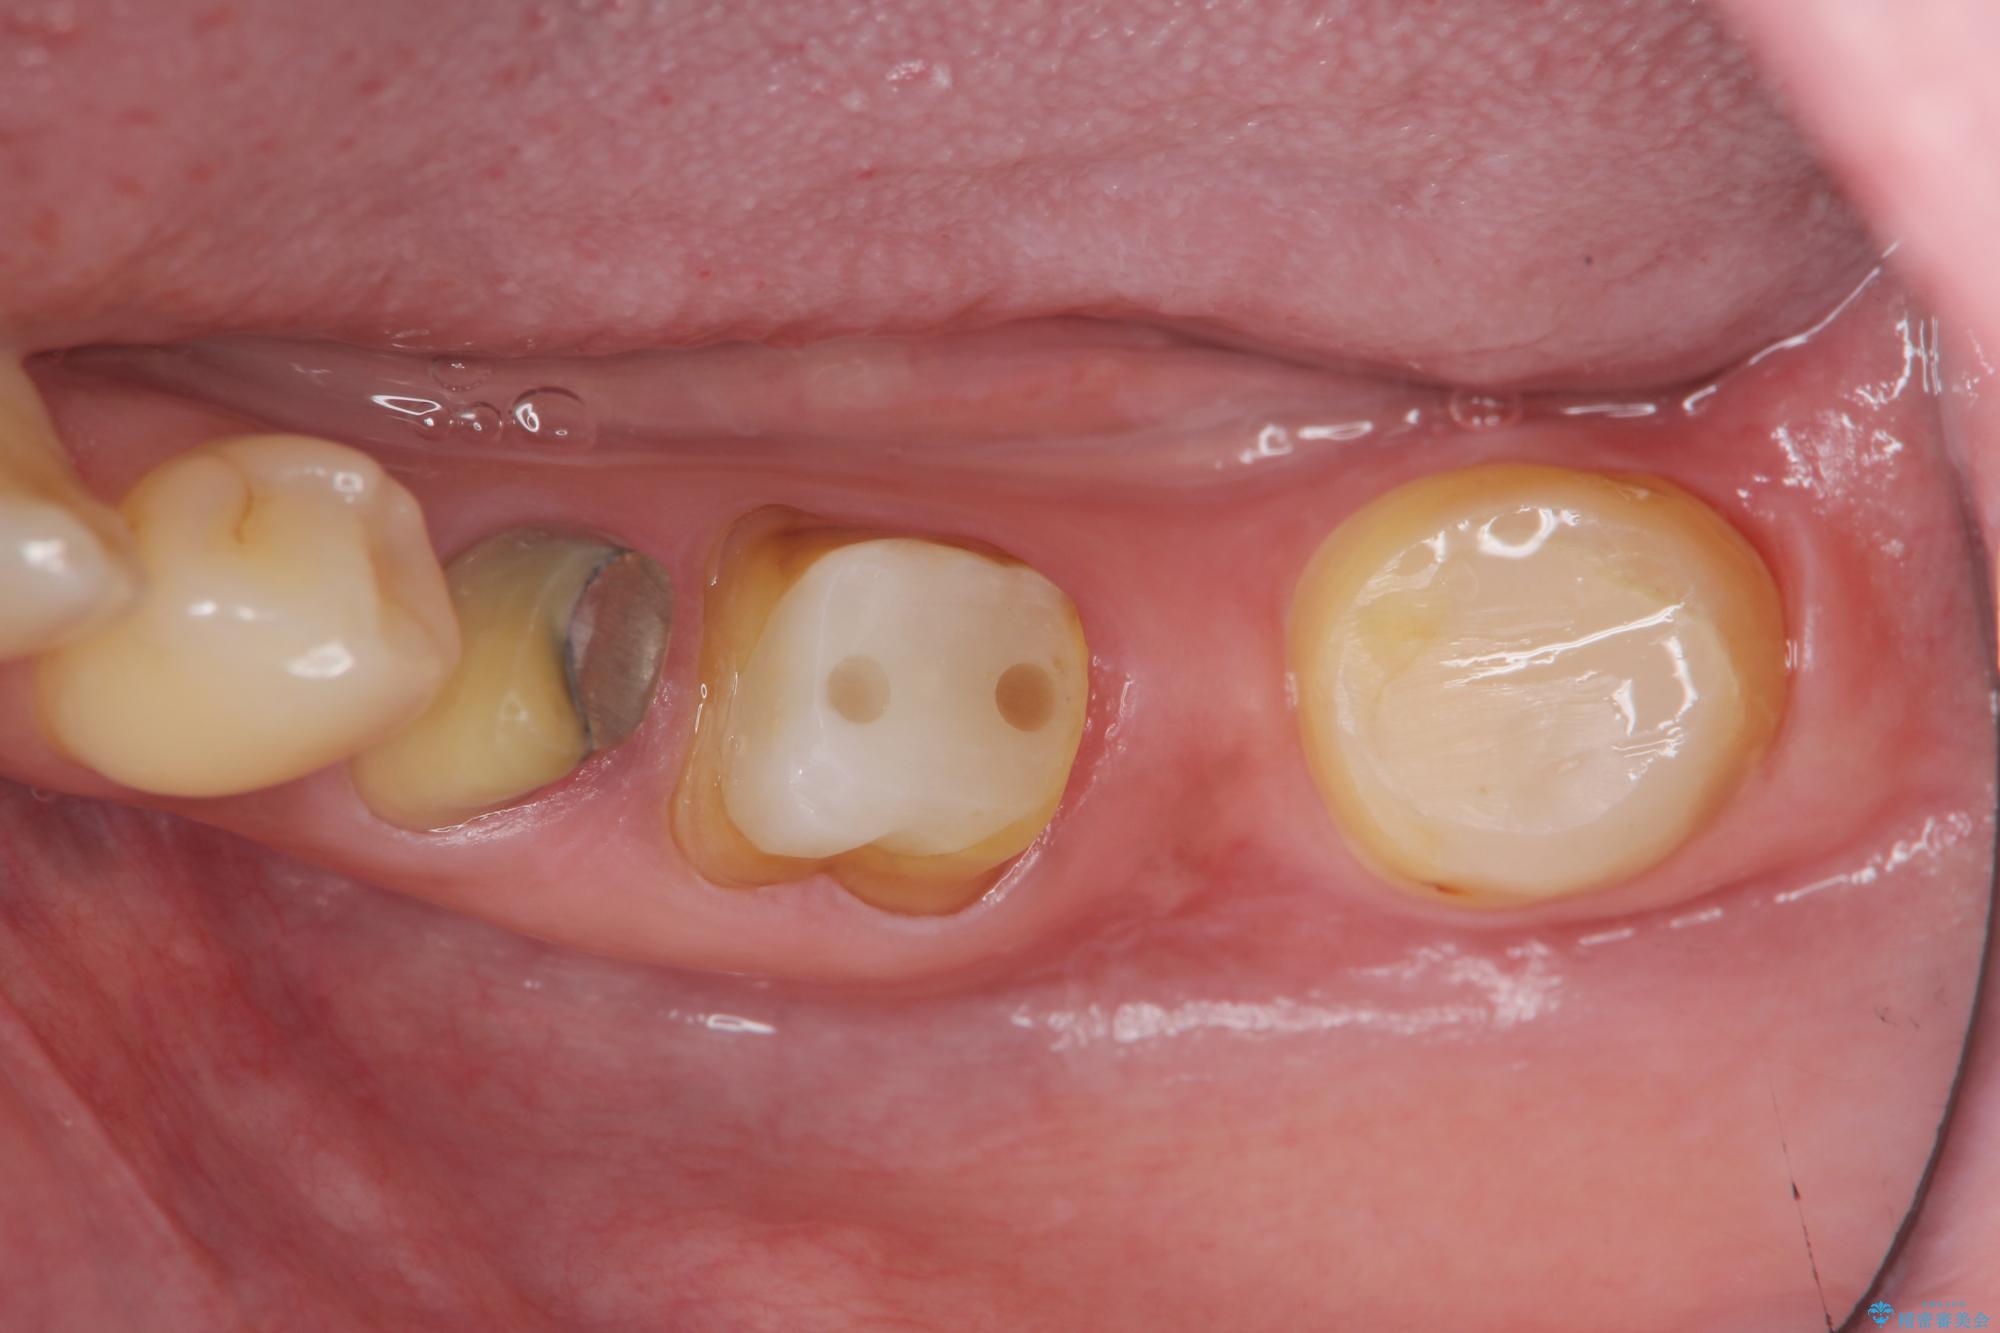

遊離歯肉移植術を併用した、破折歯のインプラント治療

- 他院で根の治療まで終え、違和感が取れず相談に来院されました。

当該歯を精査したところ、歯根に破折が見られ抜歯を余儀なくされました。

抜歯後、インプラントを用いて咬合機能を回復すると共に周囲に強固な角化歯肉を移植することによりより長期にわたり安定したインプラント周囲環境となるよう治療を計画します。

インプラント周囲の角化歯肉が存在することにより、歯ブラシがしやすくなりインプラントにトラブルが起きる確率を減らしより長期的な予後を望むことができます。